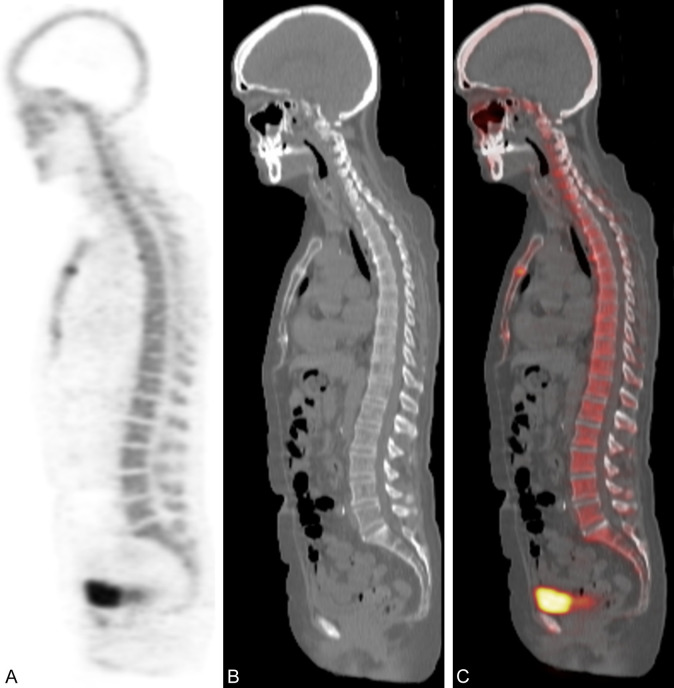

Figure 1.

Sagittal views of 18F-NaF PET (A), CT (B), and combined 18F-NaF PET/CT (C) for Case 1.

A 25-year-old female with a body mass index (BMI) of 28.1 kg/m2, no history of cardiovascular disease (CVD), a smoking history of 5 pack-years, and active alcohol consumption was recruited from the Cardiovascular Molecular Calcification Assessed by 18F-NaF PET CT (CAMONA) clinical trial (NCT01724749) [11] as a healthy volunteer. The subject underwent 18F-NaF PET/CT imaging 90 minutes after radiotracer injection (Figure 1). The mean standardized uptake value (SUVmean) for 18F-NaF in the trabecular region of each lumbar vertebral body (VB) was assessed by manual delineation of a region of interest (ROI) using OsiriX MD software (Pixmeo, Bernex, Switzerland). Specifically, the ROI was created by applying the oval function the center of the trabecular bone region throughout the consecutive axial PET/CT slices of L1 to S1 vertebrae. The size of the ROI was kept constant and placed to avoid cortical bone, vertebral arch, and facet joints. The average SUV of all voxels in the ROIs was then calculated to determine 18F-NaF SUVmean for each VB. To determine lumbar spine density, the same ROIs was used to calculate the average CT Hounsfield unit (HU) value in each VB. The following thresholds were used to distinguish lumbar osteoporosis with 88.5% specificity and 60.8% sensitivity: L1 ≤ 110 HU or L2 ≤ 100 HU or L3 ≤ 85 HU or L4 ≤ 80 HU [12].

The subject’s lumbar spine 18F-NaF SUVmean and radiodensity on CT were among the highest noted in the entire cohort of patients assessed (Table 1). The high HU values suggest no structural abnormalities.